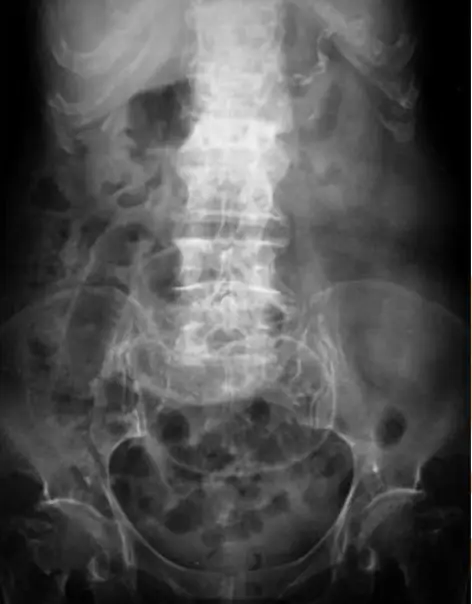

80 歲女性為長期糖尿病、高血壓及中風不良於行之病人,因急性腹痛來急診就醫,其平躺之腹部 X 光如圖 (一),另一張左側躺之腹部 X 光檢查如圖 (二),下列敘述何者正確?

Supine 腹部 X 光(圖一):

- 可見整體腸管雜亂分布的氣相(diffuse gas pattern),但無明顯廣泛氣液平面。

- 中線或上腹區出現一條中央偏淺的放射透亮月牙狀陰影,並可疑有氣體沿肝臟前緣或腹膜韌帶(falciform ligament)外緣分布,形成 cupola 或 falciform ligament sign。

→ Supine 片中游離氣體不會集中在橫膈下方,故常以上述徵象偵測(如 Rigler’s sign、falciform ligament sign、cupola sign)(ajronline.org)。